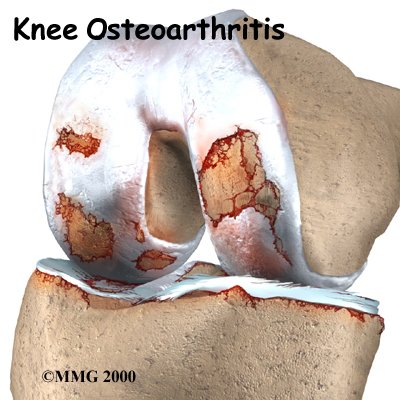

The main problem in OA is degeneration of the articular cartilage. Articular cartilage is the smooth lining that covers the ends of the leg bones where they meet to form the knee joint. The cartilage gives the joint freedom of movement by decreasing friction. The layer of bone just below the articular cartilage is called subchondral bone.

When the articular cartilage degenerates, or wears away, the bone underneath is uncovered and rubs against bone. Small outgrowths called bone spurs or osteophytes may form in the joint.